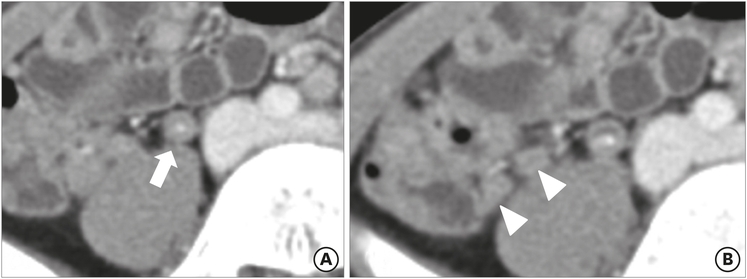

The mean maximal diameter of the appendix was 9.56 mm in the true appendicitis group and 7.28 mm in the negative appendicitis group. According to the definition of appendiceal enlargement (>8 mm in maximal diameter), 3 patients (23.1%) in the negative appendicitis group had an enlarged appendix, while 60 patients (68.2%) in the true appendicitis group had appendiceal enlargement (Fig. 1). This difference was statistically significant (p=0.002). Periappendiceal fat inflammation, or fat stranding, was noted in 2 patients (15.4%) in the negative appendicitis group and 43 patients (48.9%) in the true appendicitis group (p=0.023) (Fig. 2). For the other measured findings, there were no significant differences between the groups. The ACT findings are summarized in Table 2, along with their odds ratios and 95% confidence intervals (CIs).

Fig. 2

Preoperative ACT findings for a 13-year-old male patient, who was demonstrated to have lymphoid hyperplasia: (A) appendicolith (arrow) and (B) luminal distension (arrowheads) were observed, but there were no other diagnostic abnormalities in ACT.

ACT, abdominal computed tomography.